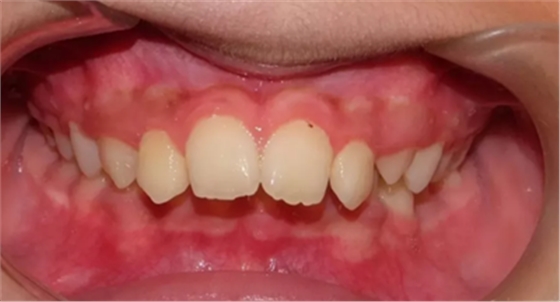

03 牙列擁擠

因虎牙特別突出、牙齒層次不齊前來就診,該如何避免?